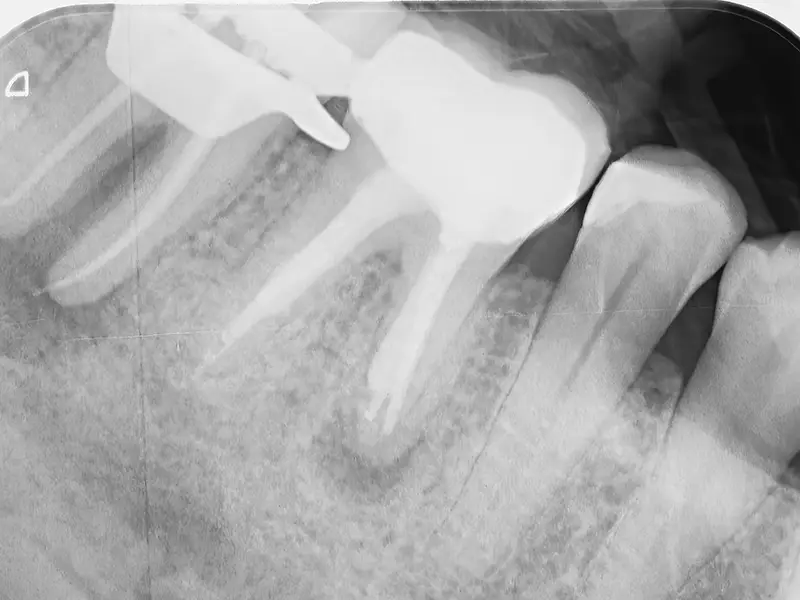

- Radiografie endorali o 3D (CBCT)

- Valutazione dello smalto e della profondità della lesione